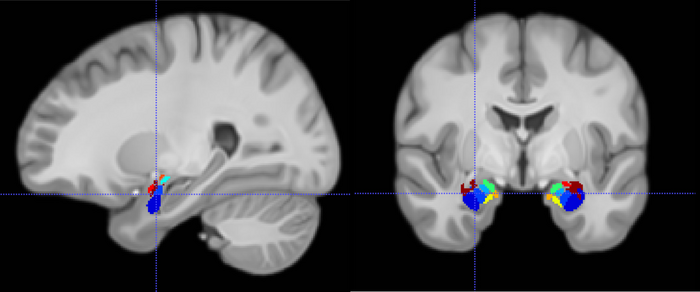

Magnetic resonance imaging depicting the location of a recording electrode in a subregion of the amygdala (colored regions).

Credit: Salman Qasim/Columbia Engineering, created using Biorender.com